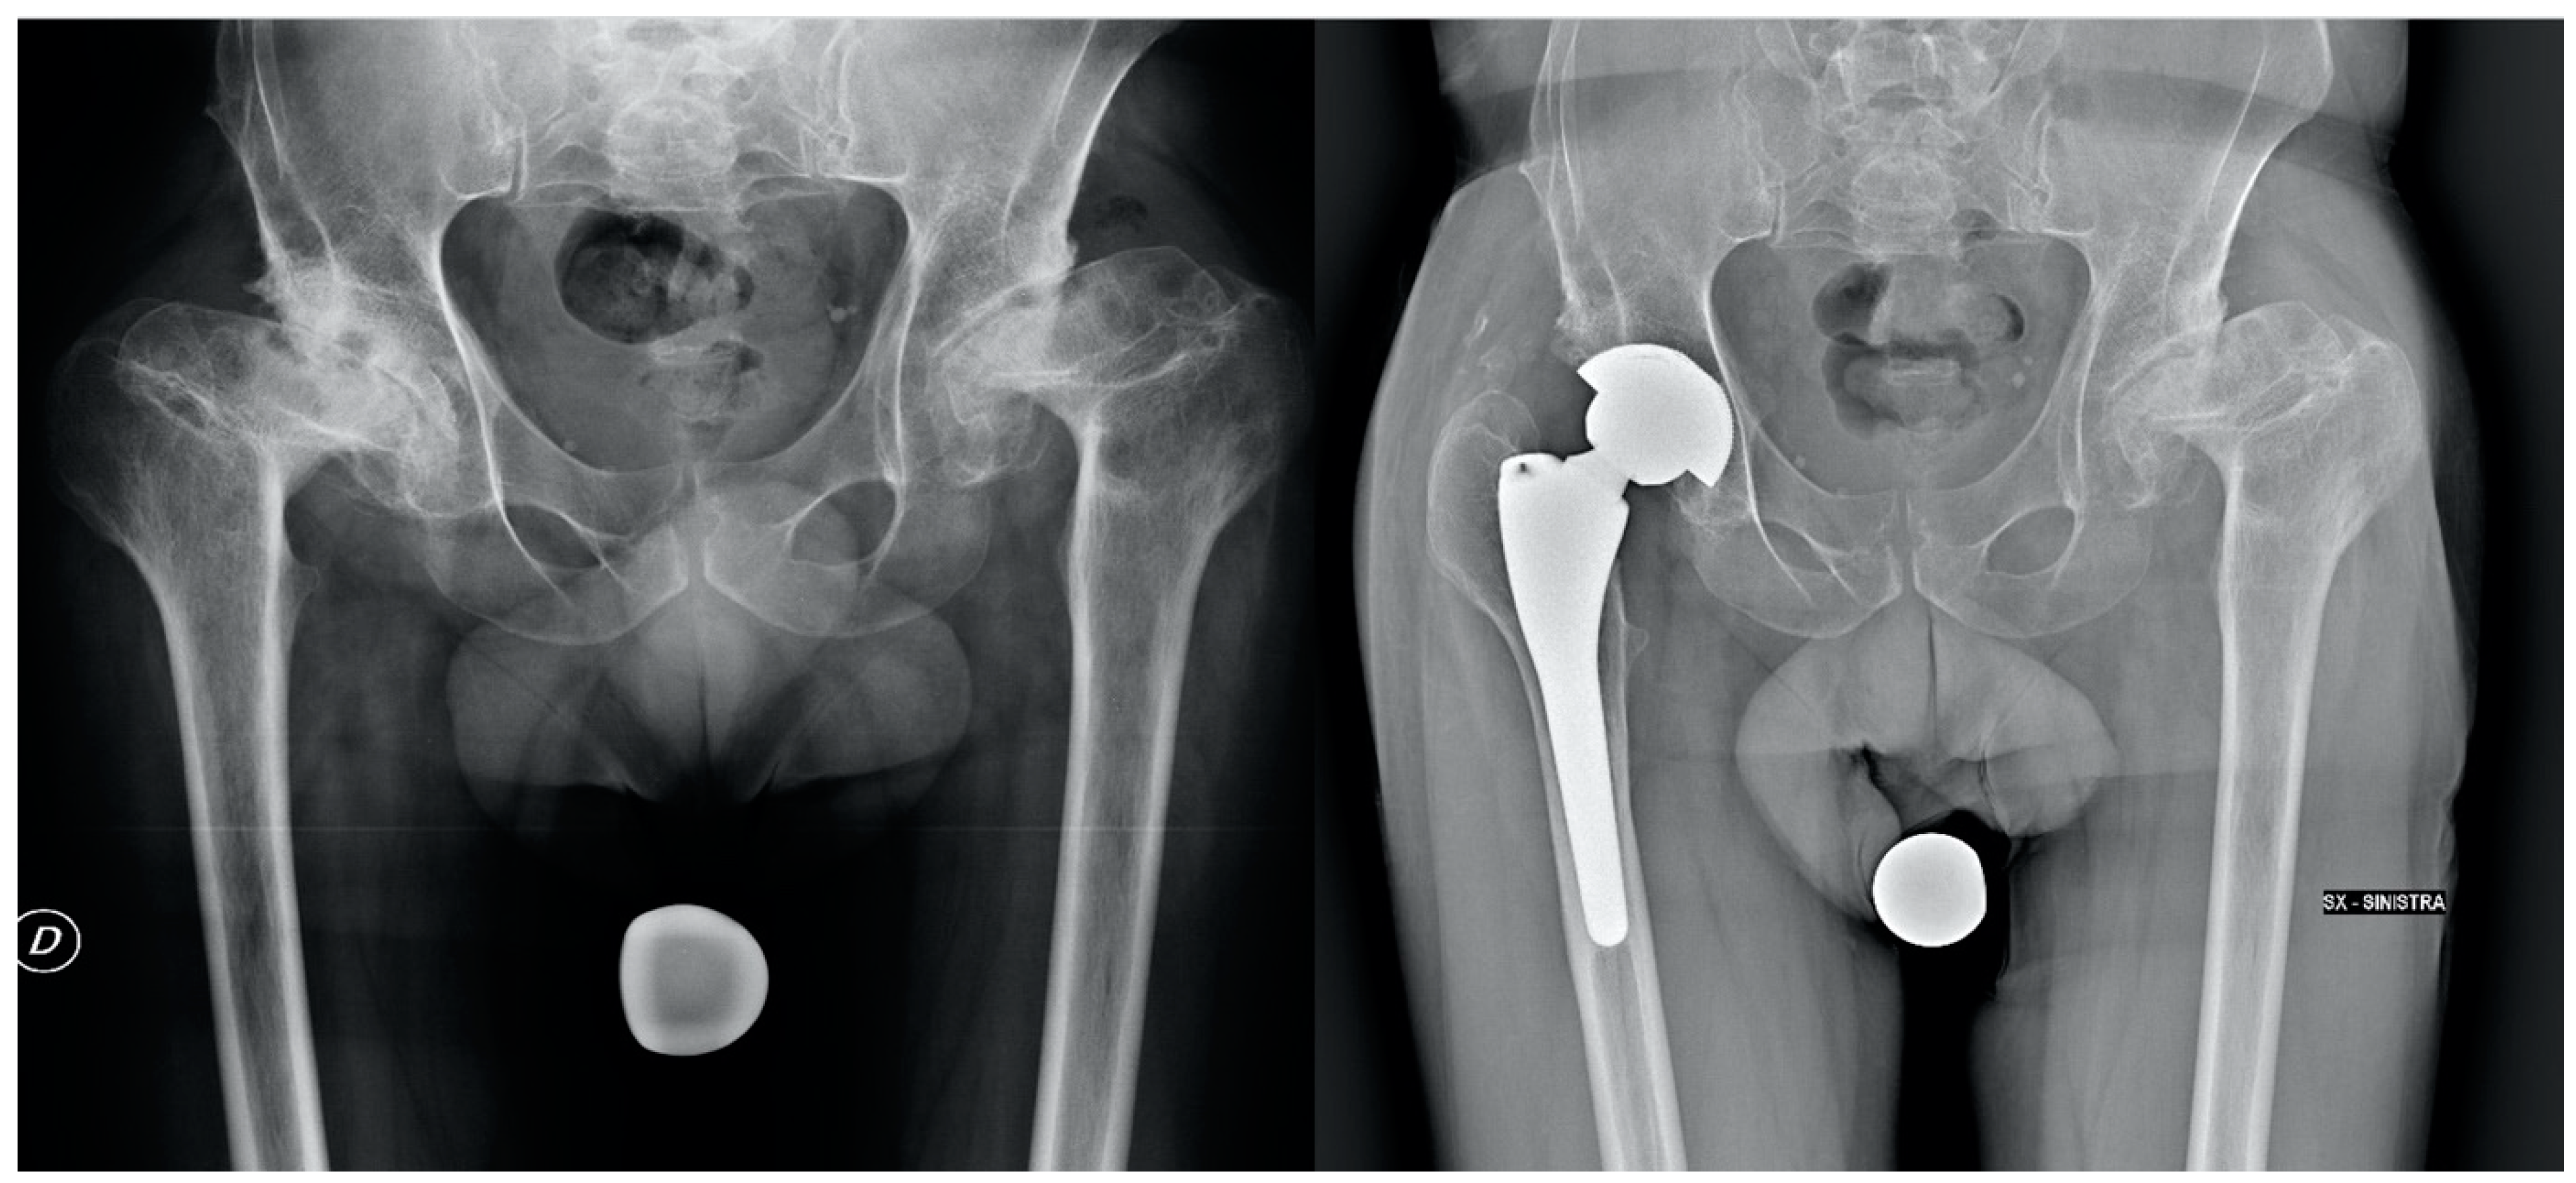

Total Hip Arthroplasty for Low-Grade Developmental Hip Dysplasia Changes the Ipsilateral Knee Alignment on the Axial and Coronal Planes

2. Materials and Methods

| Pre-operative Crowe classification | I: 26 (65%) II: 14 (35%) |